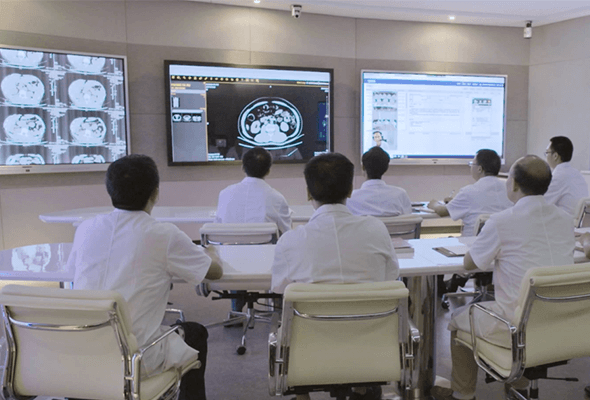

一脈陽光影像中心

一脈陽光影像醫院集團,作為國內早期創建規模龐大的集團化、連鎖化影像??漆t院,不僅已在全國近20個省市創建50余家影像專科醫院,并擁有超過300位知名專家。

南昌大學附屬第二醫院紅角洲影像中心

南昌大學第二附屬醫院紅角洲影像中心是一個集臨床、教學、科研為一體的影像中心,實和智能傾力打造,推動江西影像的發展,為贛鄱民眾提供高質量的醫療保障。

廣西省來賓市人民醫院影像中心

來賓市人民醫院影像中心的建成,實現了影像科與臨床科室的實時交互、數據同步,同時也為更多基層醫院提供便捷的影像閱片會診幫扶服務。